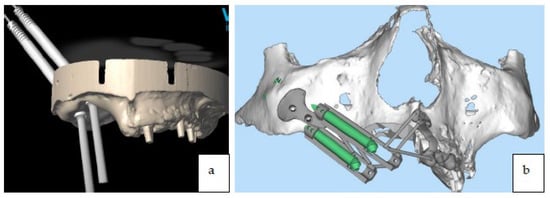

The surgical osteotomies that were planned for removal of the tumor were transferred to the digital project (Figure 4) through a dedicated software for the digital planning of implant surgery, and were printed (EZgoma©, Noris Medical Ltd., Nesher, Israel).

Figure 4.

Surgical osteotomies planned for tumor excision were transferred to the 3D printed digital model.

The surgery was programmed as: two zygomatic implant placements (length 45 mm, diameter 4.2 mm, Noris implant©) fixed on the right zygoma with emergence on sites #13 and #15), and a fix provisional full-arch prosthesis (Figure 5a,b, Figure 6a–c and Figure 7a–c).

Figure 5.

(a,b) Preoperative digital planning of implant placement.

A titanium surgical guide was manufactured using CAD/CAM technologies for the placement of the zygomatic implants along with a reinforced provisional prosthesis (titanium and Poly-methyl methacrylate (PMMA) material produced by milling with a 5-axis machine) (Figure 8a,b).

Figure 8.

(a) Titanium guide for zygomatic implant placement. (b) Titanium guide for zygomatic implant placement on stereolithographic model.